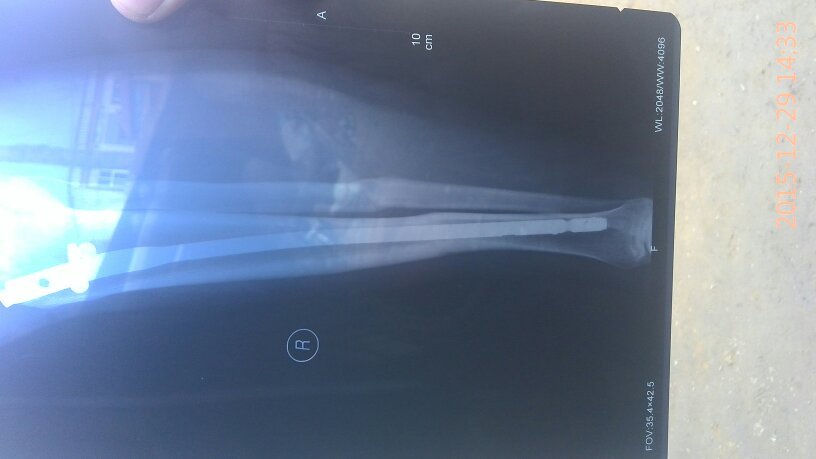

有骨科医生吗?我小腿骨折,上的钢板现在八个月了昨天复查医生说,骨头已经长好,可以取钢板了,我就是问 有骨科医生吗?我小腿骨折,上的钢板现在八个月了昨天复查医生说,骨头已经长好,可以取钢板了,我就是问问八个月了取是不是有点早,心里有点害怕,麻烦帮我看看告诉我,谢谢了…… 点击展开 匿名用户 2015-12-30 19:45 满意回答 怎么骨折的? 匿名用户 2015-12-30 20:55 宝宝知道提示您:回答为网友贡献,仅供参考。 为您推荐: 其他回答 你还是听医生的吧,时间太久了也不太好, 匿名用户 2015-12-30 20:54 没事了,别虚 匿名用户 2015-12-30 20:53 医生的话是对的 华雄40 2015-12-30 19:47 相关问题 小腿骨折钢板固定后,钢板折断且 小腿胫腓骨骨折只放了钢板没有复位这样好吗 我右小腿骨折,手术后有钢板,3个月了外伤口不愈合 是…